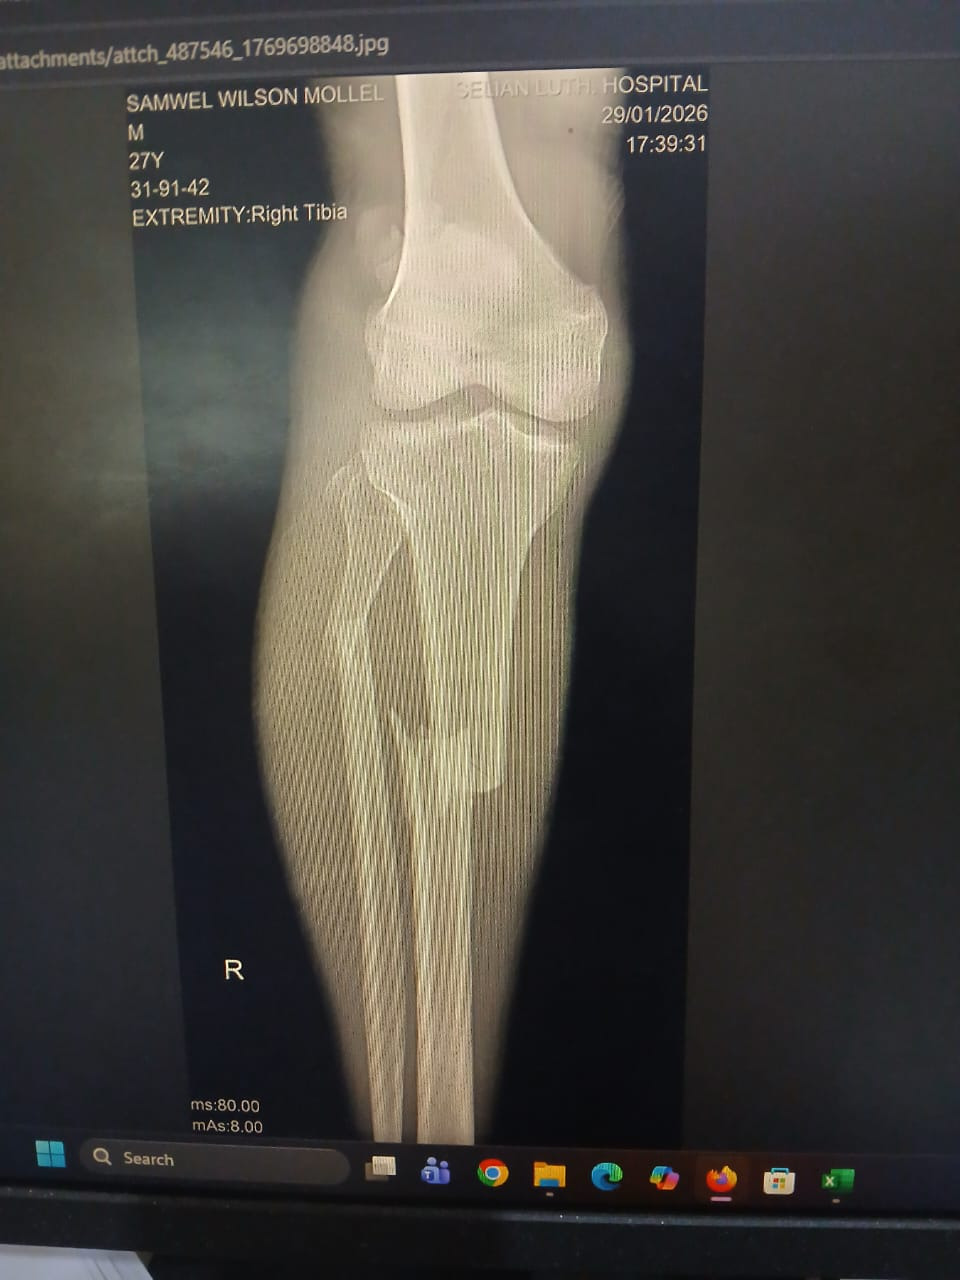

가나안감리교회(Mbalibali)에서 목회하는 잭슨목사의 동생(아루샤 거주)이 뺑소니 교통사고로 팔과 다리에

골절상을 입었습니다처음에는 가족내에서 수술과 병원비를 해결할 것이라 여기고잭슨목사에게 휴가비와

병문안 비를 주어 2주간 보냈습니다. 그러나 휴가 후 확인하니 형편이 어려워 팔은 깁스를 해 고정하였지만

다리 수술은 못했다고 하였습니다. 마음이 많이 아팠습니다. 평소에 목회 열심히 잘 하여 신뢰가 두터운

사고일시 : 2026119

사고내용 : 경제적으로 열악합니다. 다른 사람의 오토바이를 하루씩 빌려 영업을 해서 생활하는 형편입니다.

아루샤 외곽지역으로 갔다가 복귀하는 도중 뒤에서 승용차가 추돌한 사고입니다.

사고차량은 바로 뺑소니를 쳐서 피해자가 볼 수 있는 상황이 아니었고, 목격자도 없는 상태입니다.

한 참 후에 사람들이 와서 경찰에 신고했고, 병원으로 이송되었다고 합니다.

수술비 : 130만실링(75만원)

입원비 및 약값 : 40만실링(25만원)

(골절 사진)